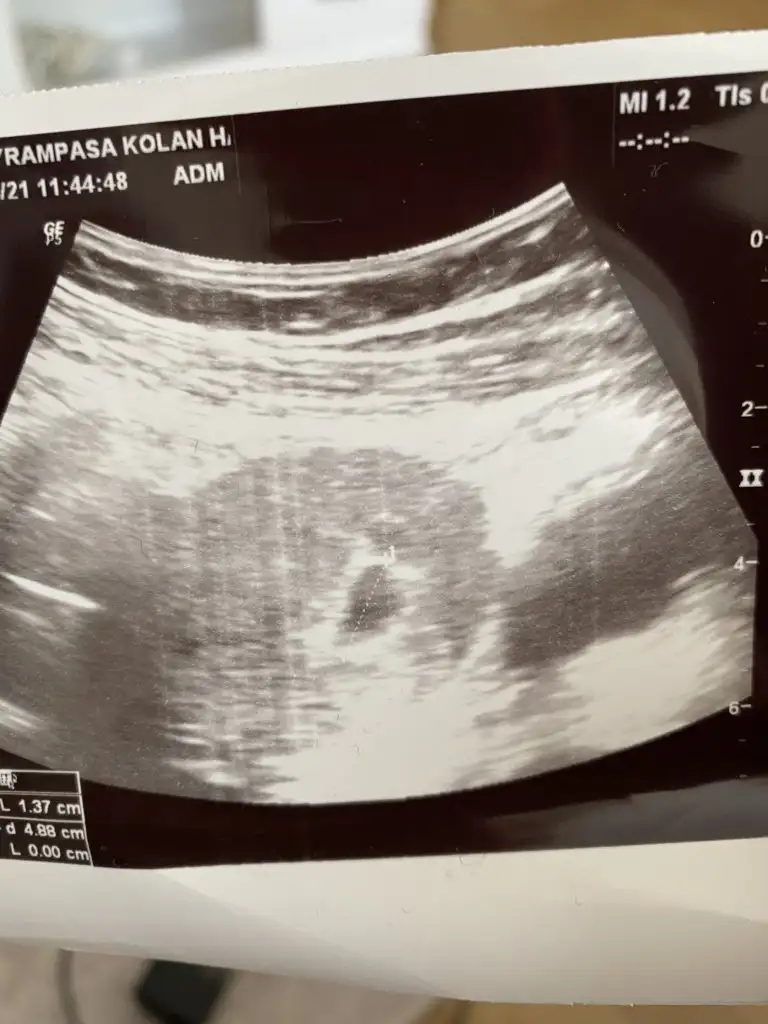

Banada bakarmisiniz

• IMG-20210427-WA0184.webp

IMG-20210427-WA0184.webp

21,5 KB · Görüntüleme: 60

• IMG-20210427-WA0181.webp

IMG-20210427-WA0181.webp

23,4 KB · Görüntüleme: 56